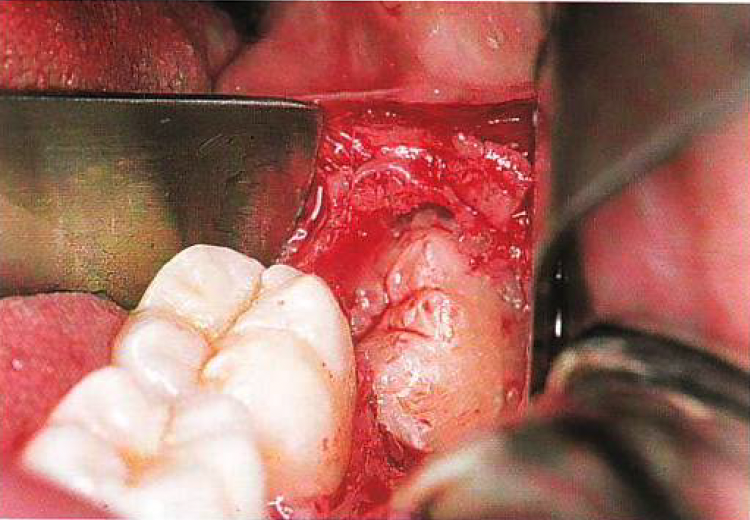

Les extractions simples deviennent rapidement complexes lorsqu’on manque d’outils, de vision ou de stratégie. Cette formation de 3 jours, donnée par un chirurgien maxillo-facial, est conçue pour les dentistes qui veulent passer au niveau supérieur et aborder les cas difficiles avec précision, confiance et maîtrise.